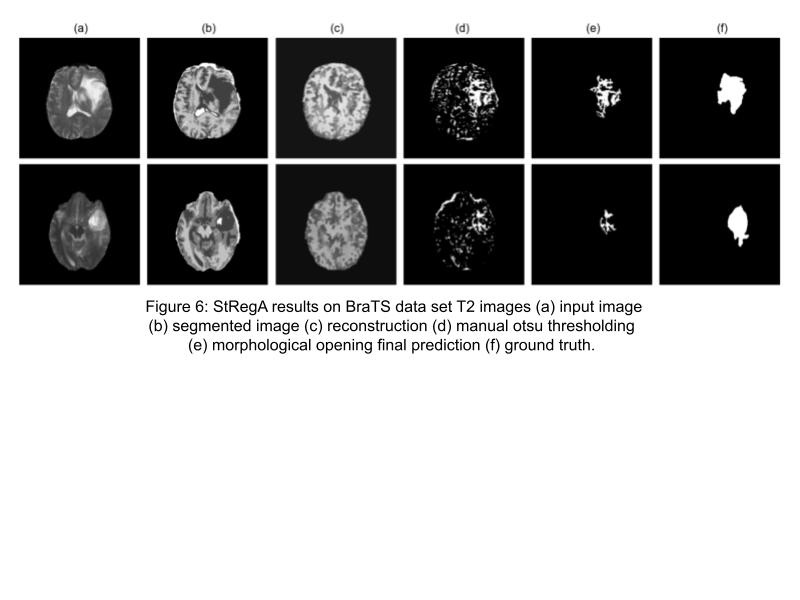

Figure 6: StRegA results on BraTS data set T2 images (a) input image (b) seg- mented image (c) reconstruction (d) manual otsu thresholding (e) morphological opening final prediction (f) ground truth.

DICE was used to evaluate both the T1 and T2 models. It can be seen in table 2 and 3 that StRegA outperformed its counterparts. The table also shows that the T2 model performs better than the T1 model. After all, this might be intuitive since tumors are more visible in T2 images. In figures 5 and 6, under-sampling is visible in every sample when comparing column (e) with the ground truth in (f). Once again, the T2 model performs better here with their final outcome being closer to the ground truth than the T1 model even though under-sampling is present. It is worth mentioning that the T1 model was trained with regular T1 images but tested with T1 contrast enhanced images, it is unknown how this affected the performance of the model if at all. What was noticeable about the performance of the model was that subtle anomalies were not detected, this can be seen in the second row of figure 5. That subtle anomaly was in a T1 image, it is unknown if the T2 model would have recognized an anomaly of similar size. If it does, then maybe the T2 model should be standard. Overall, reconstructing subtle anomalies with an acceptable error rate (labeling it as normal) is a shortcoming of reconstruction methods, especially with VAE approaches.